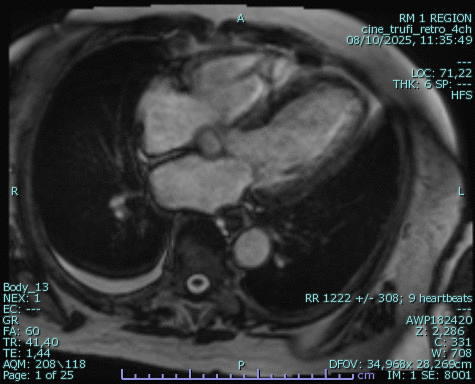

Resonancia Magnética Cardíaca (RM Cardíaca)

La resonancia magnética cardíaca utiliza campos magnéticos (no rayos X) para estudiar el corazón en movimiento y evaluar su tejido de forma detallada.

Evalúa la función y fuerza del músculo cardíaco.

Detecta inflamación, fibrosis o cicatrices.

Diagnostica cardiopatías congénitas.

Evalúa miocarditis, cardiomiopatías y secuelas de infarto.